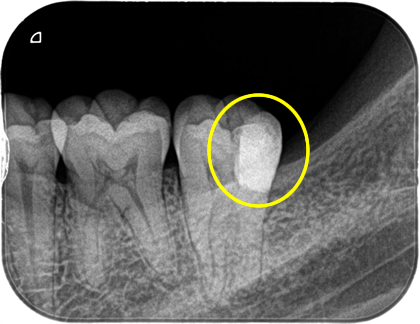

上の写真のケースでは、むし歯が神経まで達していましたが、マイクロスコープを使用して、歯髄保存療法とダイレクトボンディングで神経を保存、歯の切削量も必要最小限で治療を行うことができました。

しかし、本来は虫歯になる前に親知らずを抜歯しておけば、このような処置は必要なかった可能性もあります。親知らずが埋伏していて気になった場合には、早めの診査・治療をお勧めします。